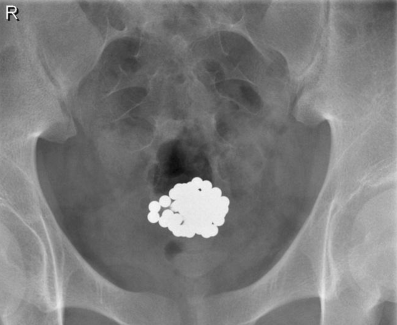

In het Maastricht UMC+ werd op de polikliniek Urologie een 17-jarige gezonde jongeman gezien, die was doorverwezen door de huisarts met dysurie en hematurie bij een urineweginfectie. De huisarts startte in eerste instantie antibiotische behandeling, echter, na enkele weken keerden de klachten terug. Bij doorvragen vermeldde de patiënt dat hij zes weken daarvoor meerdere magneetkralen via de urethra had ingebracht, met als beweegreden seksuele stimulatie uit te lokken. De patiënt dacht de kralen spontaan te kunnen lozen. Hij had in het geheel geen klachten van de kralen gehad, tot de urineweginfectie was opgetreden. Hij voelde alleen ‘iets’ kantelen in zijn onderbuik bij bukken. Bij röntgenonderzoek werd een cluster van bolvormige metaalhoudende corpora aliena gezien ter hoogte van de blaas (fig. 1). Op de operatiekamer is initieel gepoogd om de magneetkralen transurethraal te verwijderen middels een paktang (Storz) met twee rechte bekdelen. Pogingen in een magneetkraal te isoleren van het geclusterde geheel faalde echter vanwege de magnetische kracht van de kralen. Bovendien raakte het instrumentarium zelf gemagnetiseerd. Na demagnetisatie van het instrumentarium, werd een sectio alta uitgevoerd. Er werden in totaal 57 magneetkralen verwijderd, met een individuele diameter van 5,0 mm (fig. 2).

Figuur 1

Röntgenfoto van het bekken waarop ter hoogte van de blaas een cluster bolvormige metaalhoudende corpora aliena te zien is.